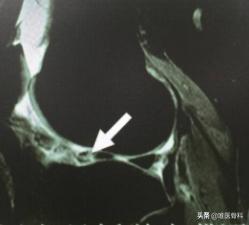

2、影像学检查

半月板损伤后可以到医院去做膝关节核磁共振检查,通过磁共振影响可以看到半月板损伤范围和损伤程度。